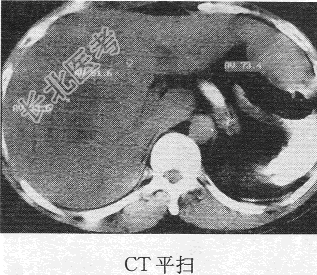

- 单项选择题患者男,49岁。发现乙肝十余年, 反复腹痛,腹胀黄疸1个月余, CT图像如下,最有可能诊断为

A、肝癌

B、肝肉瘤

C、肝再生结节

D、肝腺瘤

E、肝血管瘤